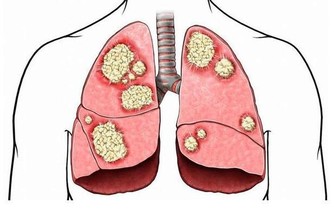

此外,大腸中腐敗食物和細菌產生的毒素,如果不能及時排出,被機體吸收後可使內臟功能而發生障礙,增加自身“中毒”的機會,便秘、便血、腹瀉、腸易激、排便惡臭、放臭屁、口臭、膚色粗糙晦暗、直腸癌急其他消化系統疾病隨之而來。

2、黑木耳豐富的纖維素和一種特殊的植物膠原能夠減少食物中脂肪的吸收及促進胃腸蠕動,防止肥胖和便秘,預防直腸癌及其它消化系統癌症的作用。

4、糙米糙米中含有豐富的B族維生素、維生素E,為腸道輸送源源不斷的能量。其中的鉀、鎂、鋅、鐵、錳等微量元素,以及大量膳食纖維,可以促進腸道有益菌增殖,預防便秘和腸癌。

6、芹菜芹菜在經過腸內消化時可以產生木質素,這是一種很強的抗氧化劑,有效抑制腸道內產生致癌物,能幫助“粑粑”在最短的時間內排除體外。